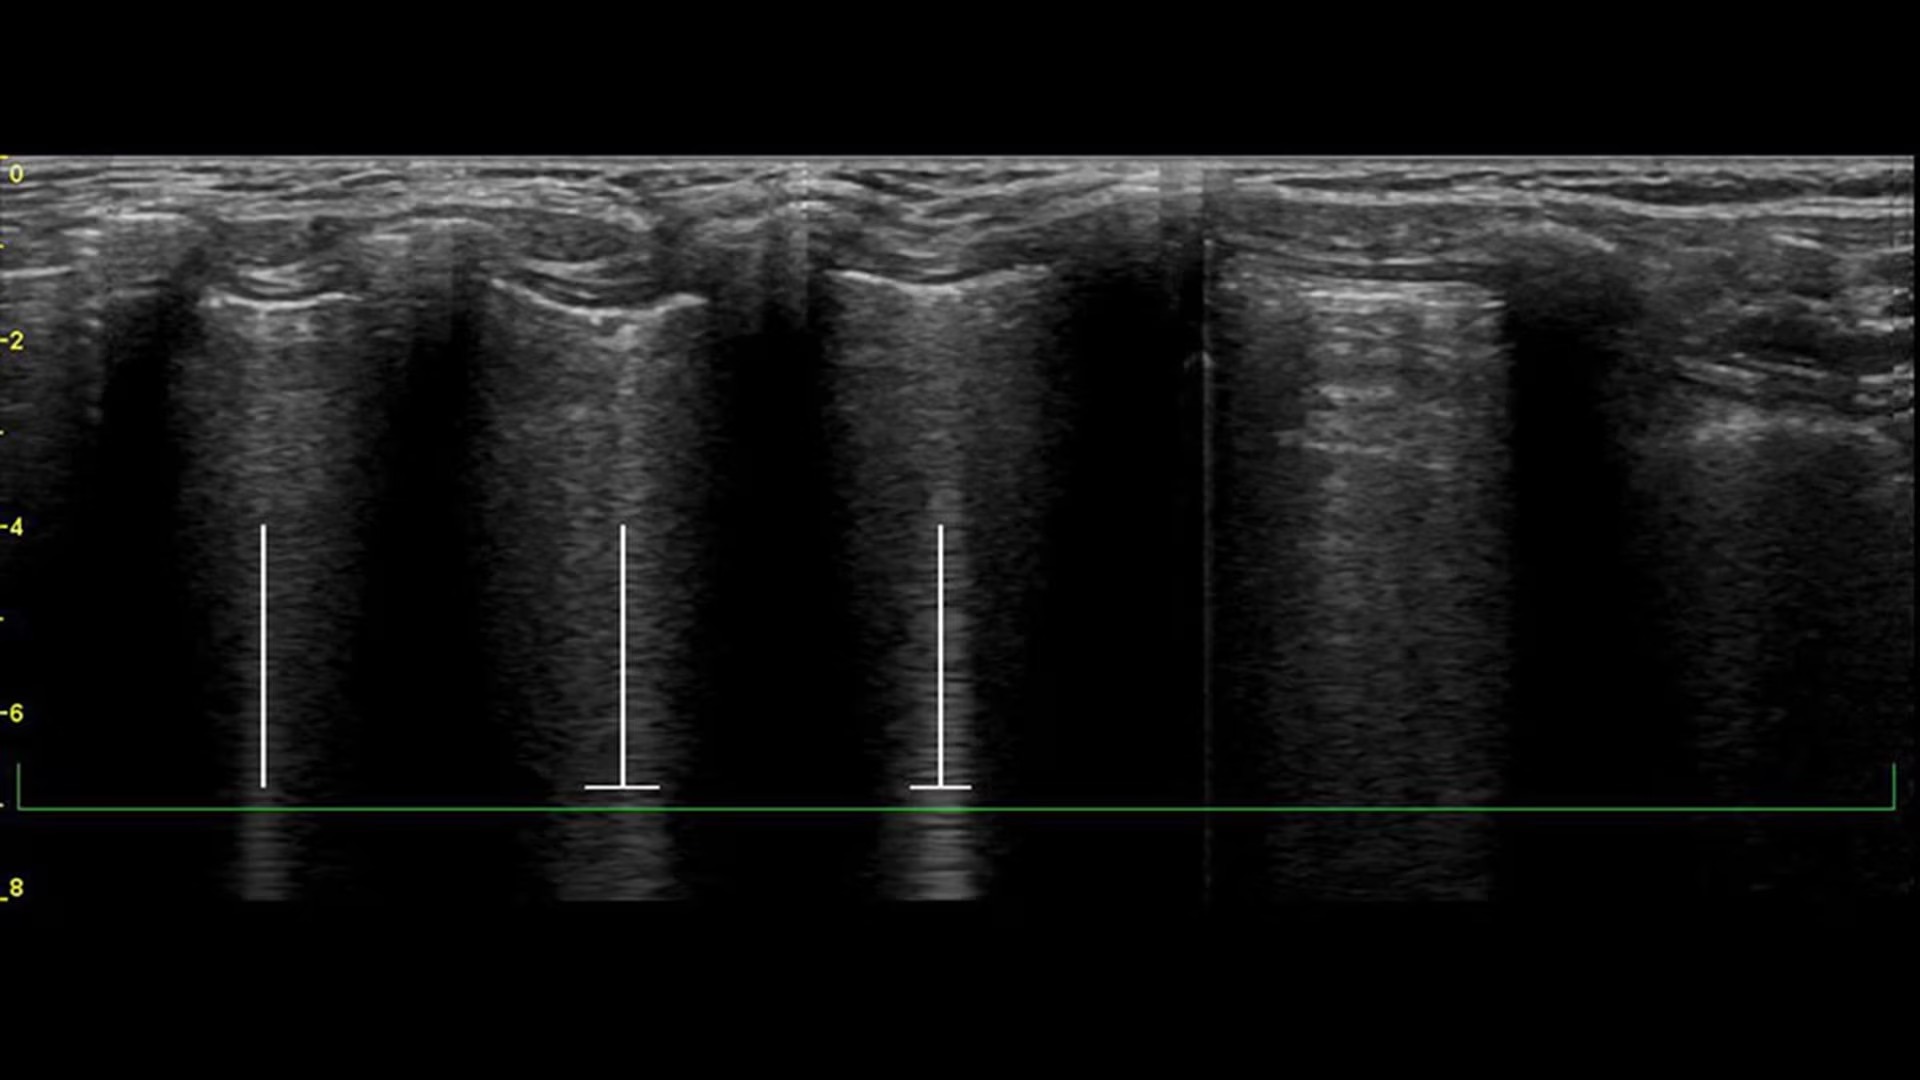

Visualize the entire lung with Lung Sweep

Lung Sweep provides a dynamic panoramic view of the entire lung. It activates when the probe taps the body and deactivates when the probe is lifted, so there’s no need to touch the screen.